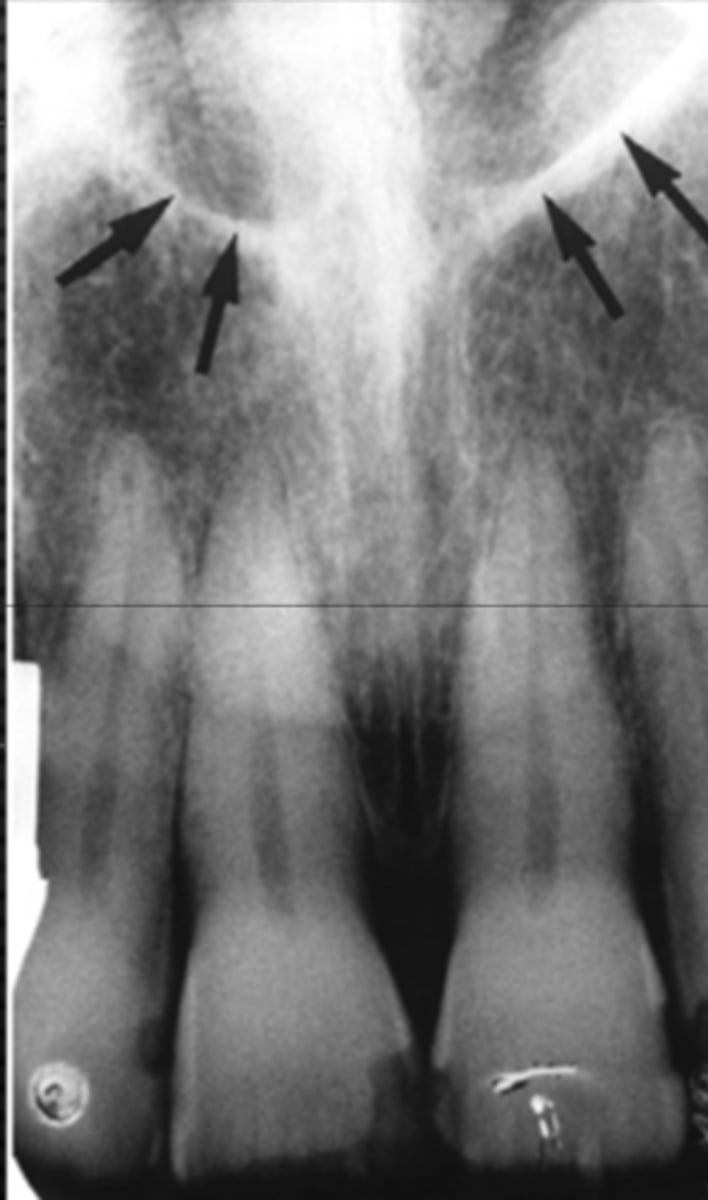

Nasopalatine (incisive) foramen

Identify the round, ovoid radiolucent structure indicated by the black arrows.

<p>Identify the round, ovoid radiolucent structure indicated by the black arrows.</p>

Nasopalatine canal

Identify the straight, radiopaque lines indicated by the white arrows.

<p>Identify the straight, radiopaque lines indicated by the white arrows.</p>

Superior foramina of the nasopalatine duct

Name the two round radiolucencies indicated.

<p>Name the two round radiolucencies indicated.</p>

Nasopalatine duct

What is the wide, vertical structure indicated by the arrows?

<p>What is the wide, vertical structure indicated by the arrows?</p>